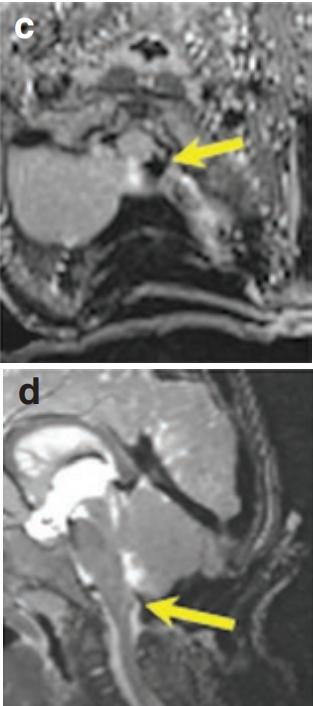

病例中的男婴Nick最初表现为头部持续左倾、眼球外展受限以及反复喉炎发作。MRI检查显示左侧延髓存在胶质瘤并伴有扩展性生长。

经过全面评估,患儿父母最终选择由INC巴特朗菲教授主刀手术。手术在术中磁共振和神经电生理监测双重保障下进行,采用俯卧位肿瘤全切术。术中影像确认肿瘤完全切除,无残留病灶。

通过枕后正中开颅入路,术中使用CUSA刀切除肿瘤。在左侧延髓外侧隐窝处发现肿瘤与后组颅神经粘连,通过精细分离成功保留颅神经功能,特别注重保护吞咽功能相关的第九、十、十一对颅神经。

术后两周患儿恢复良好,长期随访显示术后三年MRI复查无肿瘤复发迹象。患儿神经功能完好,健康成长。